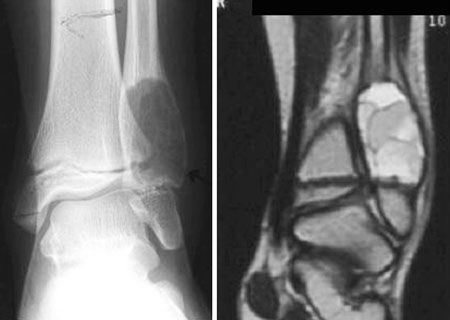

Actualité Chirurgie du pied : innovations et banque de tissu , Thibault Leemjrise Foot Ankle Institute, Clinique du Parc Léopold. 38, Rue Froissart, 1040 Bruxelles , P. Maldague Foot Ankle Institute, Clinique du Parc Léopold. 38, Rue Froissart, 1040 Bruxelles , B. Devos Bevernage Foot Ankle Institute, Clinique du Parc Léopold. 38, Rue Froissart, 1040 Bruxelles N°154 - Mai 2006 ● 16 min de lecture